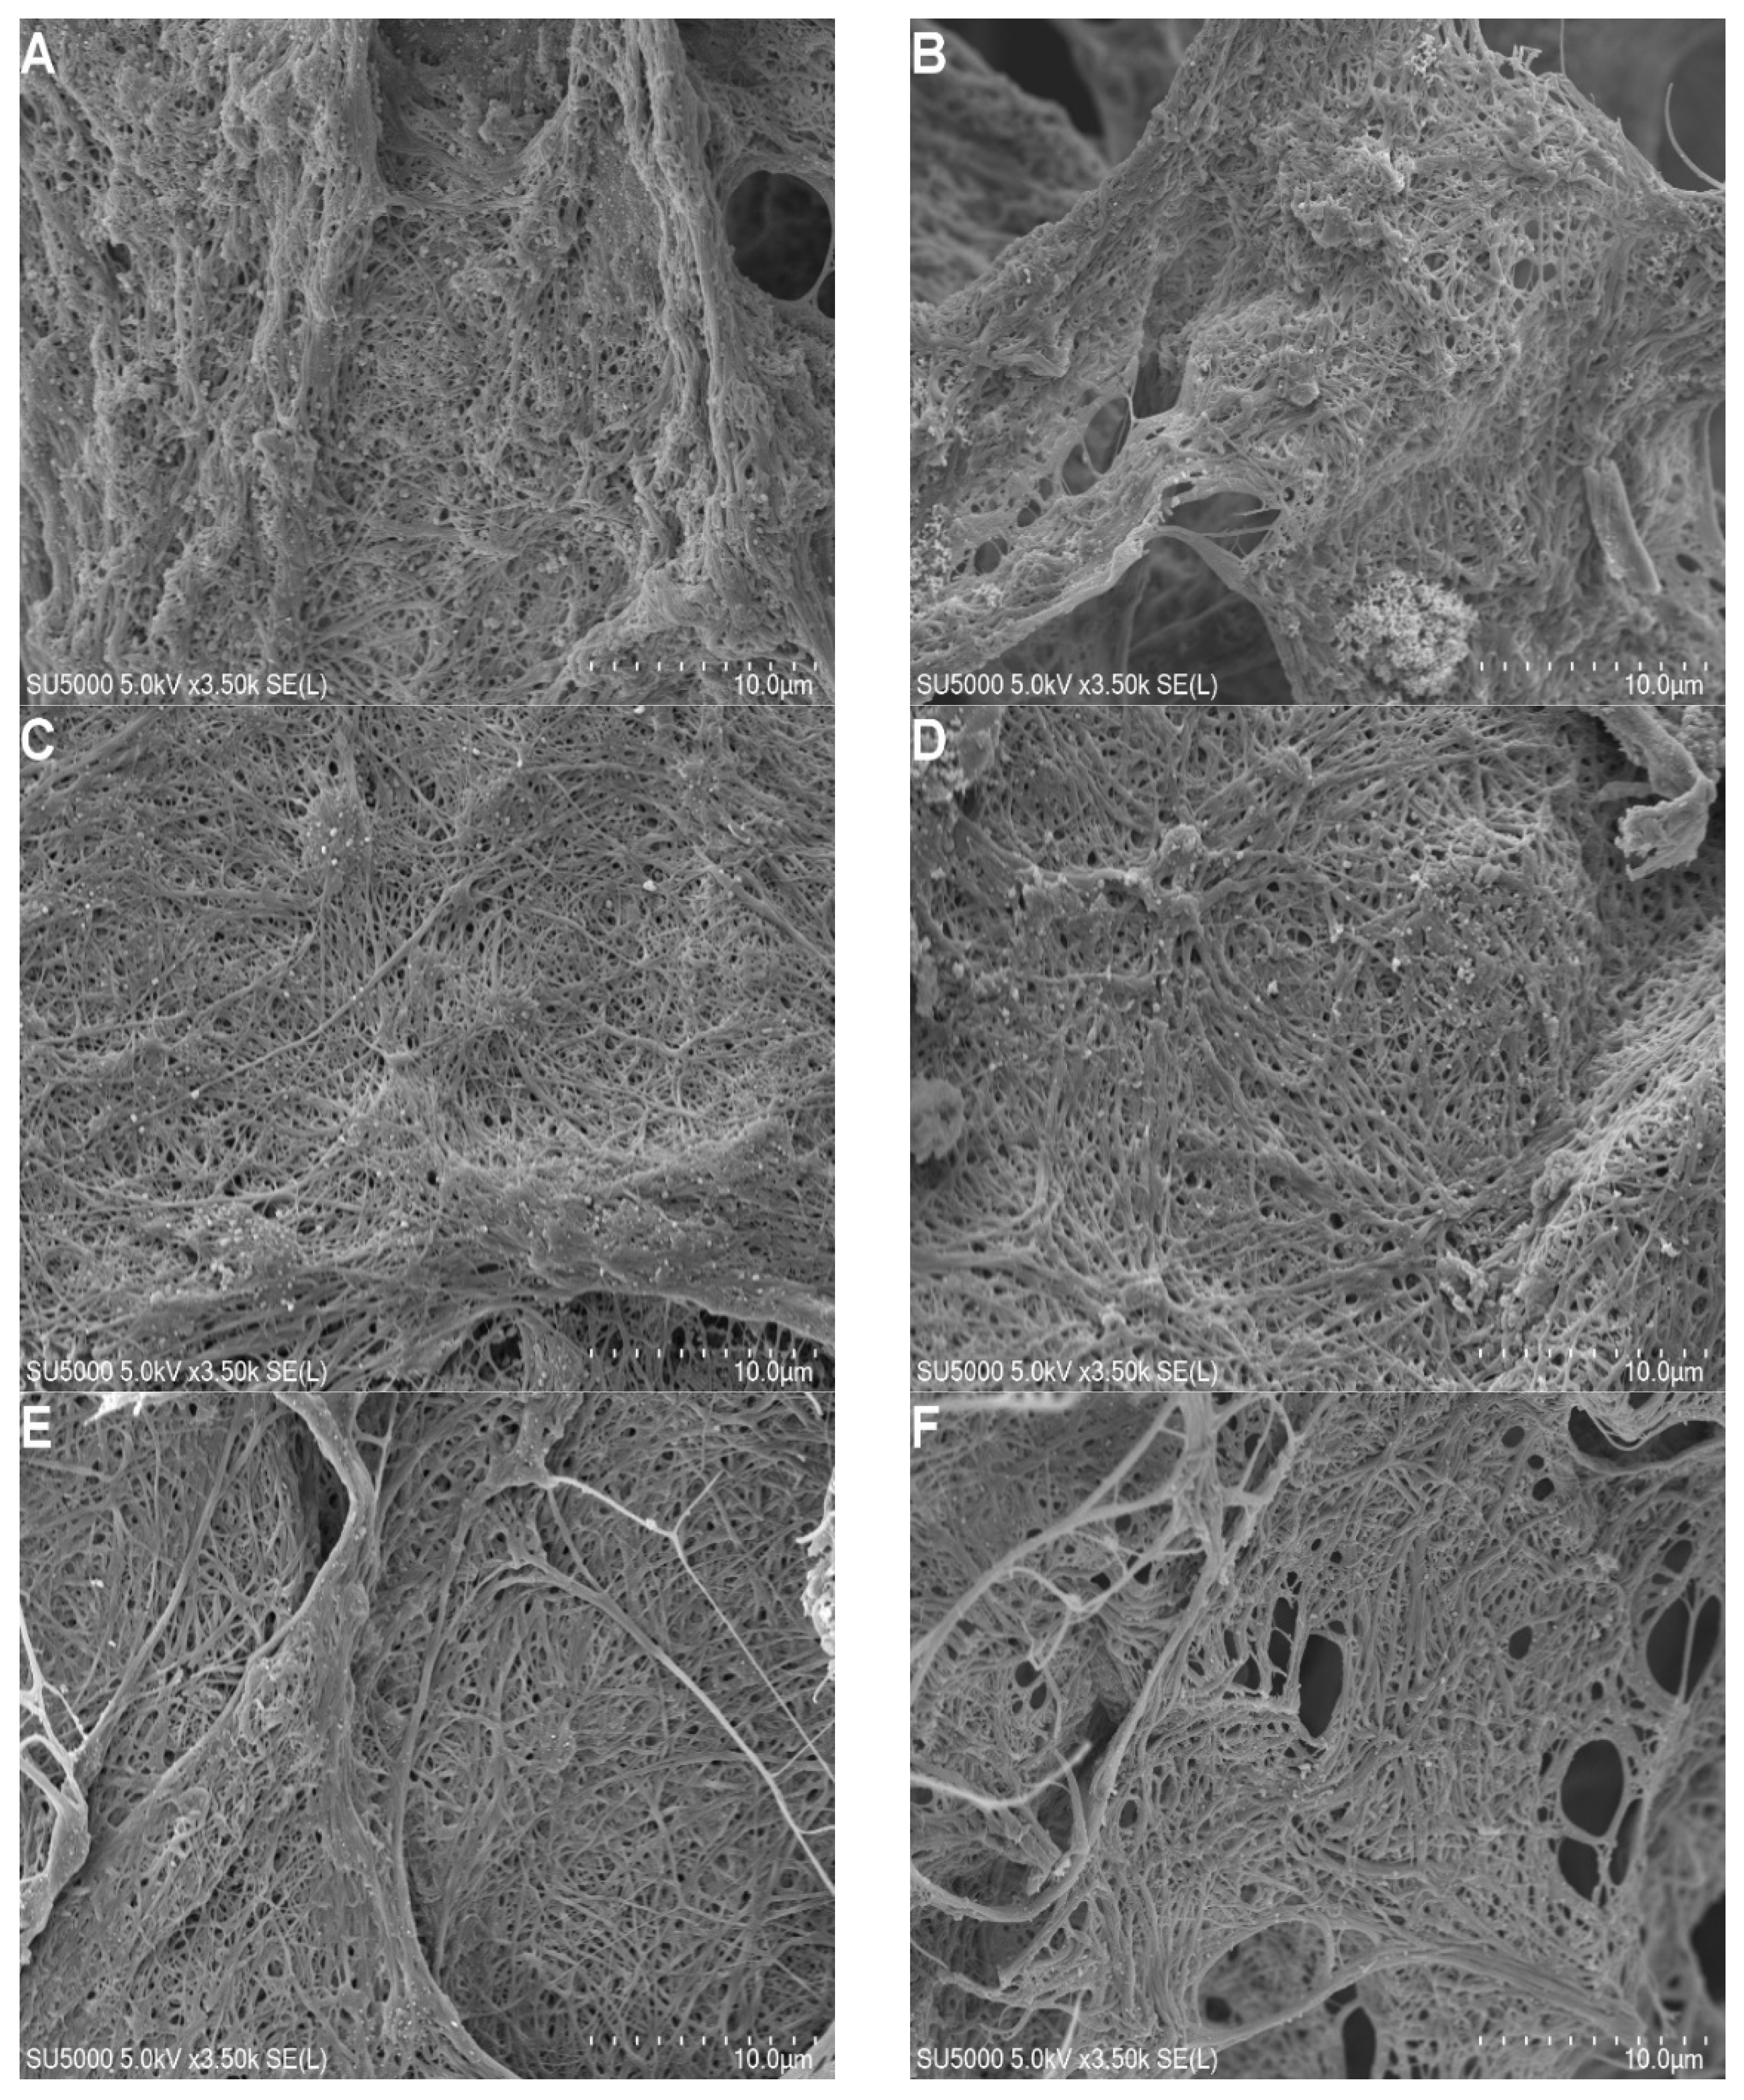

2.3. FGFC1 Effect on Fibrin Fiber Nanostructure by Scanning Electron Microscopy

4.5. Scanning Electron Microscopy